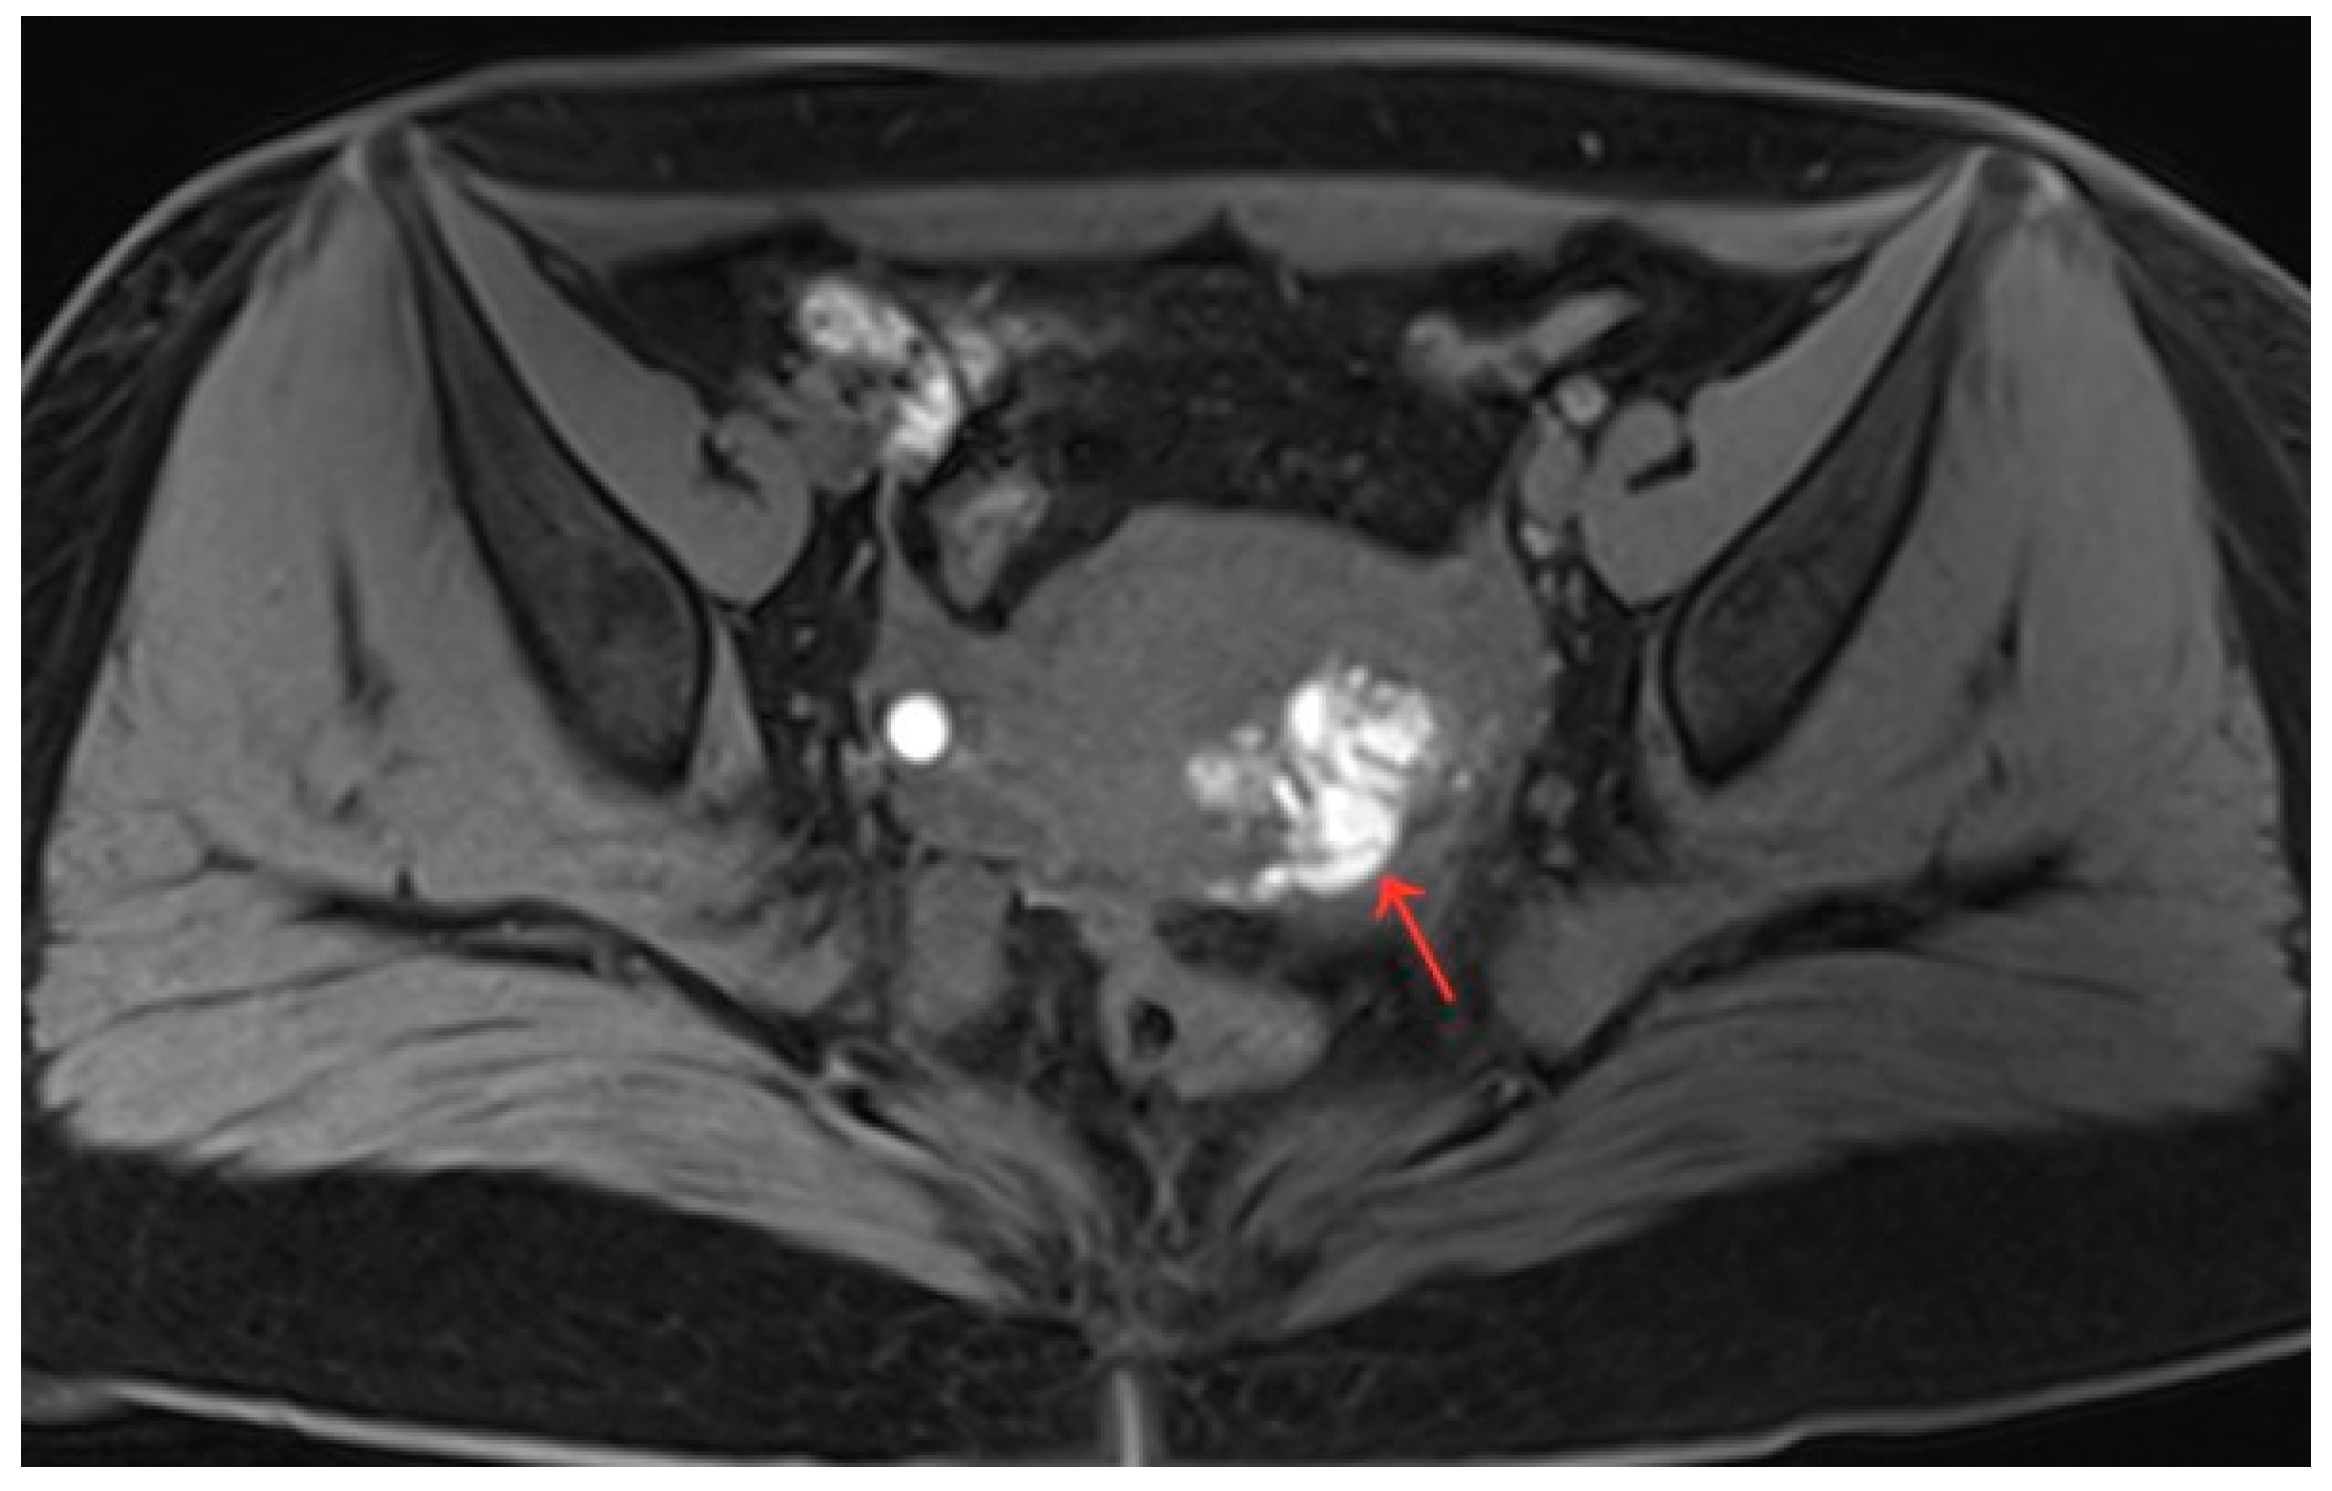

Figure 4.

Pelvic MRI shows lesions after HIFU treatment (5th year) (red arrows).